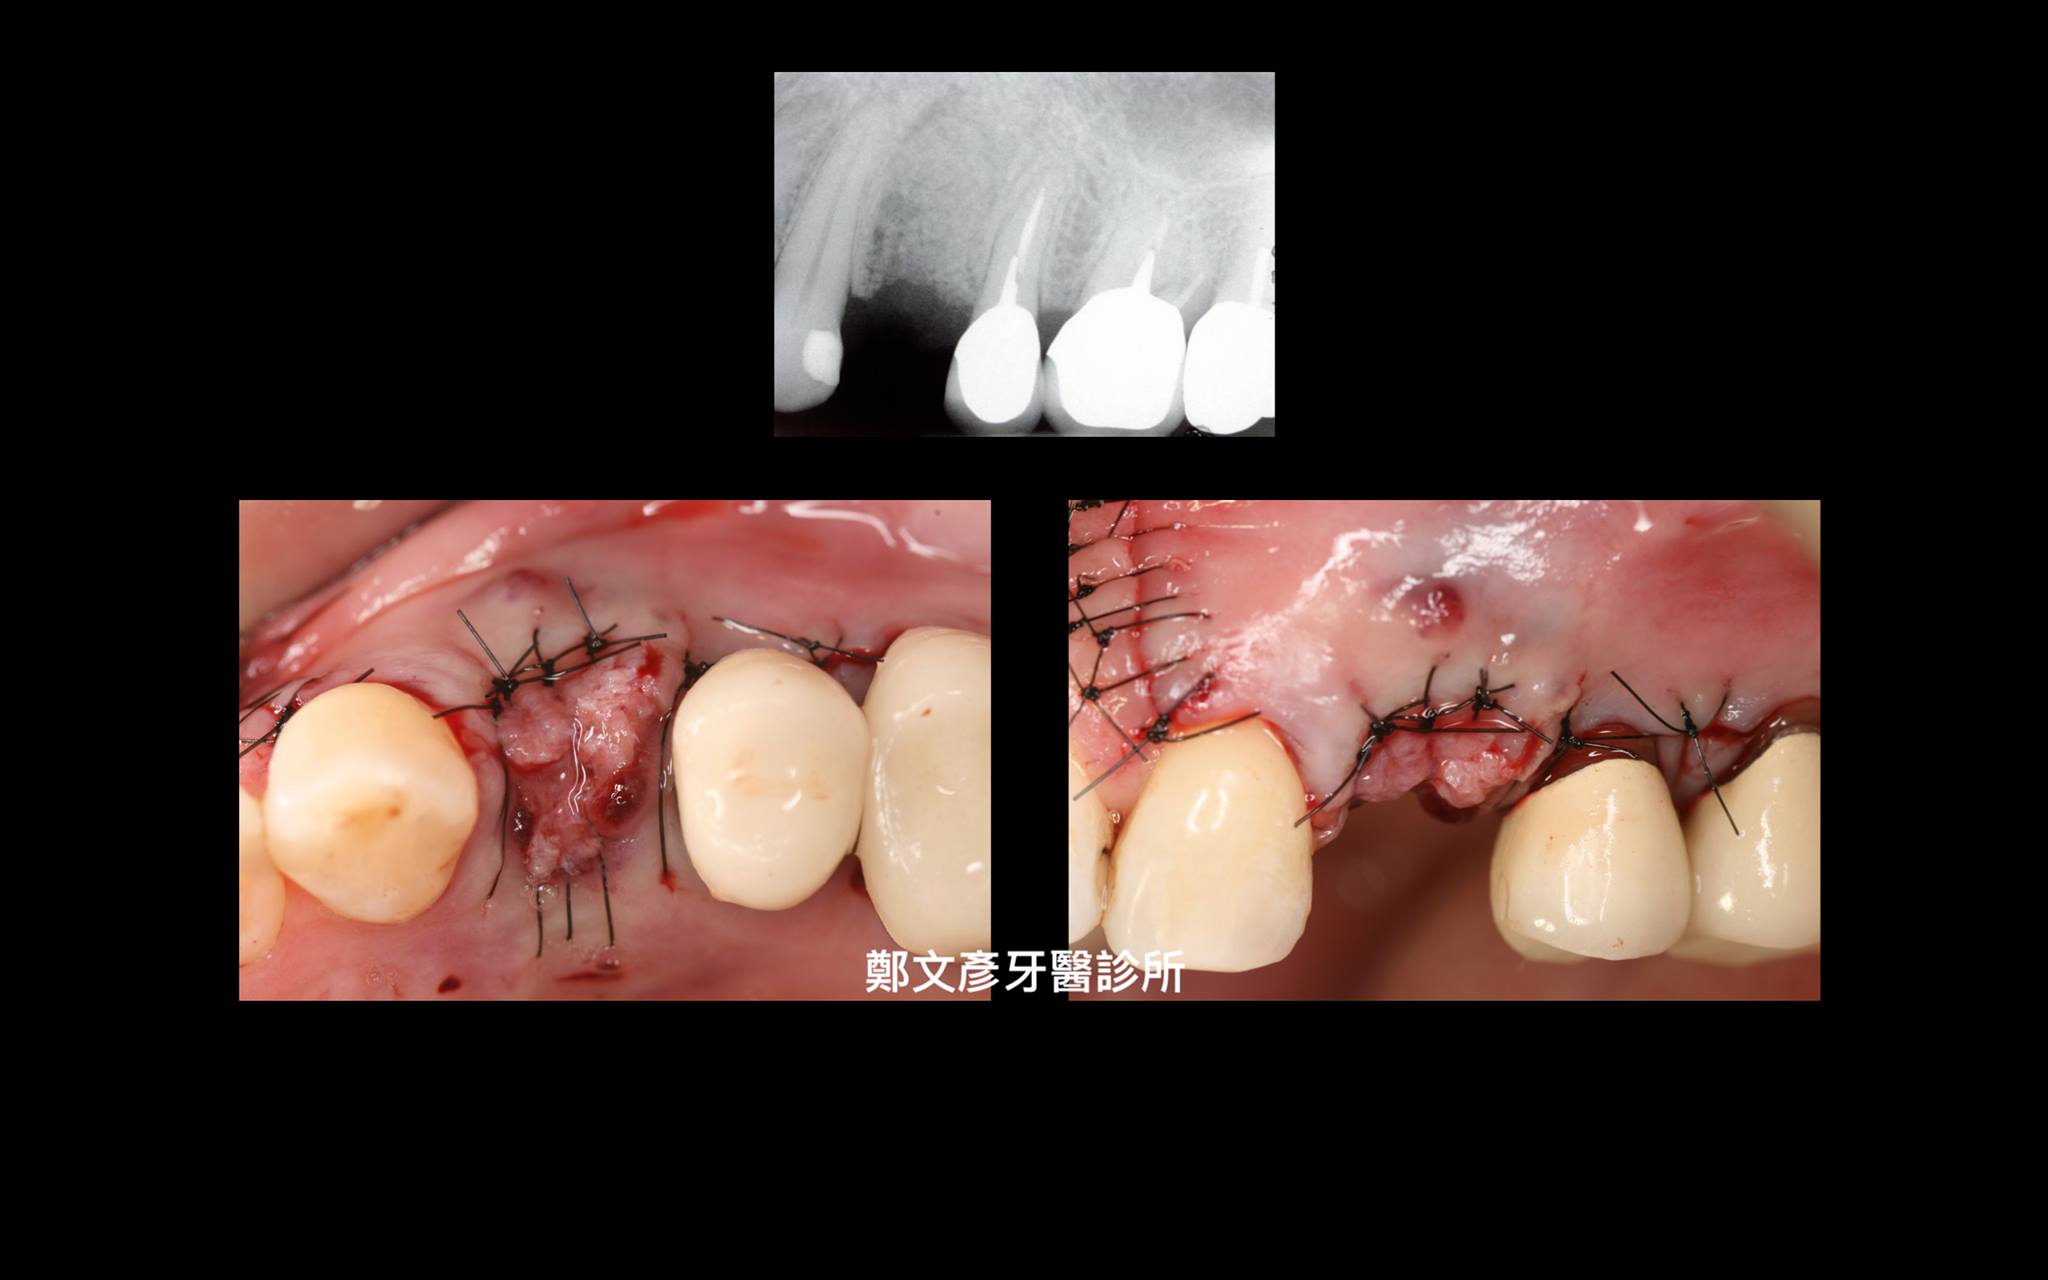

3. Role of granulation tissue in socket preservation

Role of granulation tissue in socket preservation